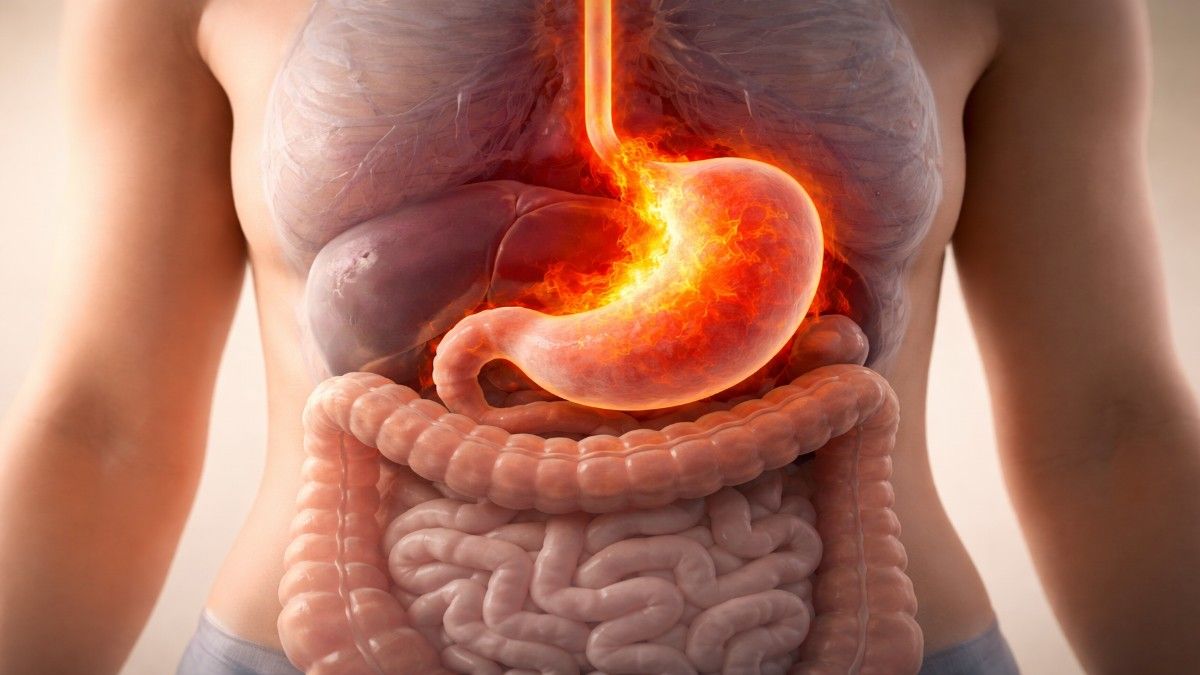

एसिडिटी तब होती है जब पेट में बनने वाला एसिड भोजन को पचाने की बजाय उलटा बढ़कर गैस्ट्रिक वॉल को प्रभावित करता है। यह एसिड जब भोजन नली (Food Pipe) तक पहुंचता है, तब जलन और दर्द जैसी परेशानियां होती हैं।

शरीर इस असंतुलन को तुरंत महसूस करता है और कई तरीके से आपको संकेत देता है।

यह शरीर का सीधा संदेश है—पेट में एसिड ज्यादा बन रहा है।